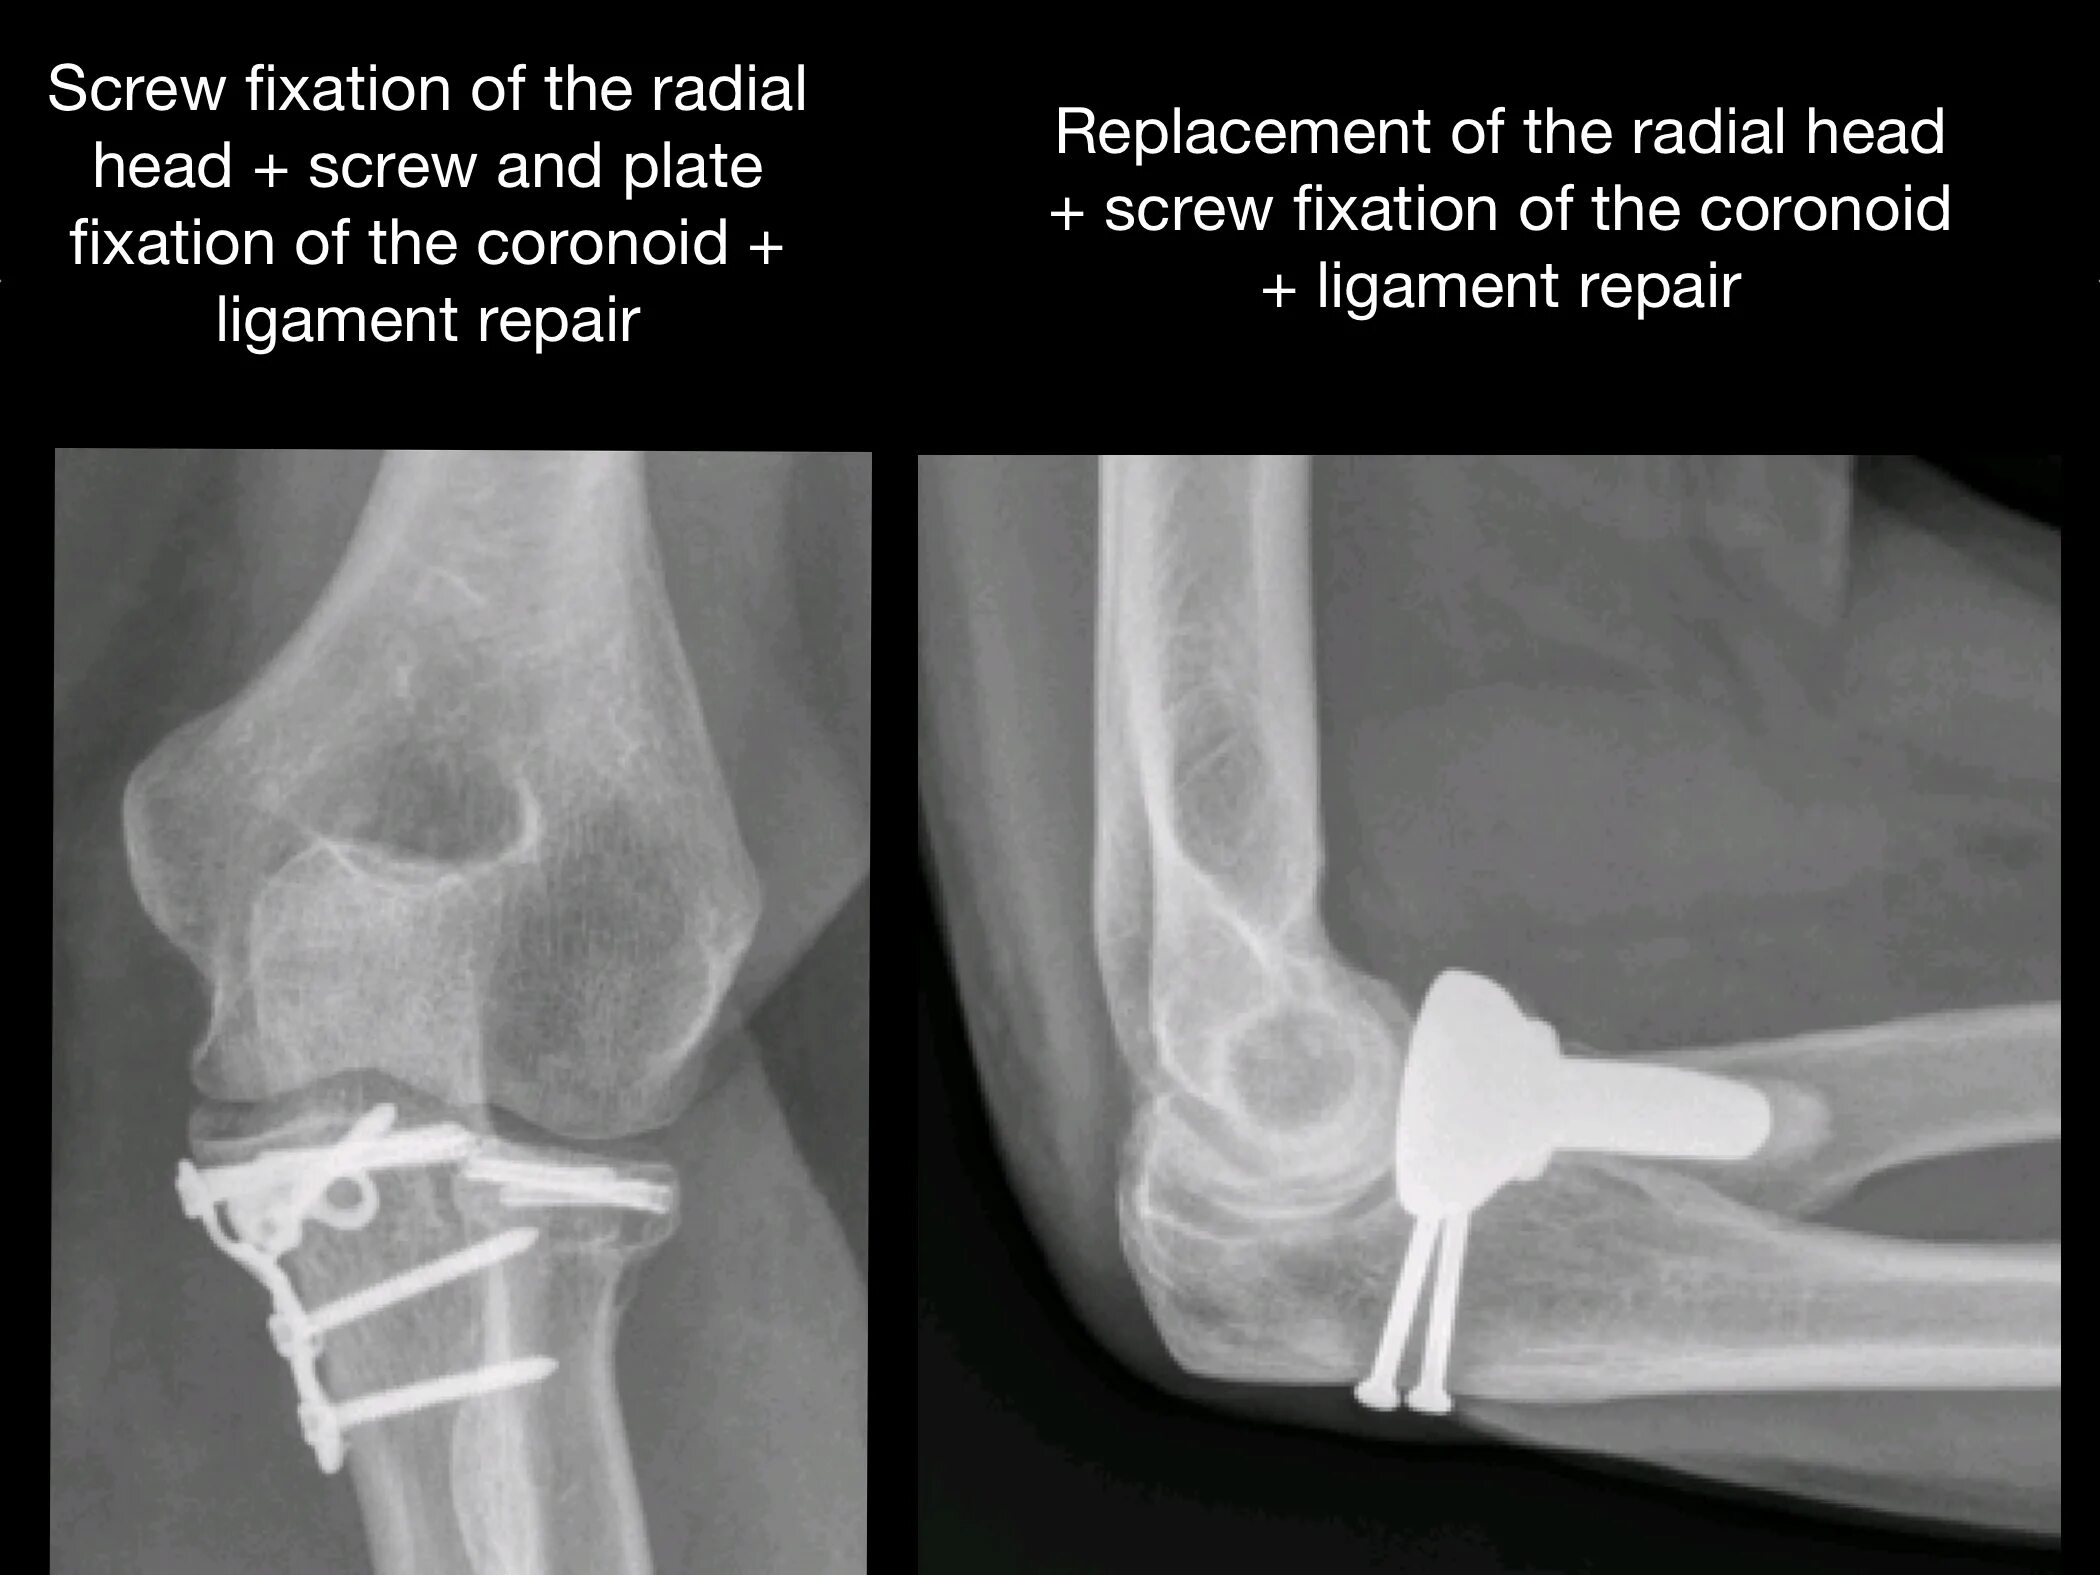

Перелом локтевой